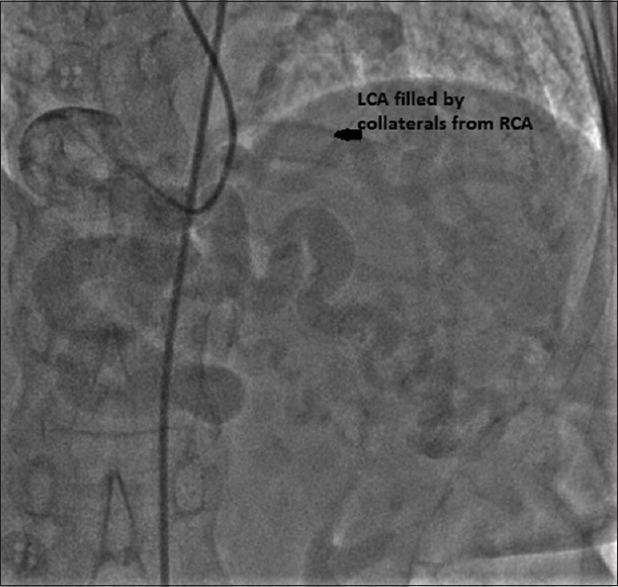

Congenital coronary artery anomalies as a whole are uncommon. Abnormal origin of the left coronary artery from the pulmonary artery (ALCAPA) is probably the most common congenital coronary defect. An overwhelming majority of the patients with untreated ALCAPA do not survive to adulthood. As yet, there is no consensus on the management of adults with ALCAPA. We describe a patient with breast malignancy and incidentally detected ALCAPA; primacy was given to treatment of the oncologic condition as a first step. Anesthesia management was focused on maintaining adequate collateral coronary perfusion and avoidance of excessive loading of the left ventricle. This was achieved using a simplified transthoracic echocardiography (TTE) protocol at the time of induction of anesthesia; TTE was also used to reconfirm the absence of disturbances in myocardial function at the end of surgery. We sugggest the routine use of tte in managing perioperative care in low resource settings when the underlying cardiac disease is rare and the evidence base if often insufficient.

先天性冠状动脉异常总体上并不常见。左冠状动脉起源于肺动脉(ALCAPA)可能是最常见的先天性冠状动脉缺陷。绝大多数未经治疗的ALCAPA患者无法存活至成年。迄今为止,对于成年ALCAPA患者的治疗尚无共识。我们描述了一名患有乳腺恶性肿瘤且偶然发现ALCAPA的患者;第一步优先治疗肿瘤疾病。麻醉管理的重点是维持足够的冠状动脉侧支灌注并避免左心室负荷过重。这是通过在麻醉诱导时使用简化的经胸超声心动图(TTE)方案实现的;手术结束时也使用TTE再次确认心肌功能无异常。我们建议,当潜在的心脏疾病罕见且证据基础通常不足时,在资源匮乏地区的围手术期护理管理中常规使用TTE。